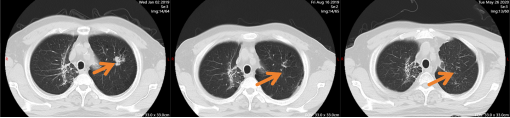

平静的日子延续到2019年初,一次常规复查时,影像科医生发现张大叔左上肺出现一枚新发结节。肺穿刺活检结果提示“肺腺癌”,且基因检测未发现可靶向的突变位点。针对这一情况,医院立即启动多学科会诊(MDT):胸外科专家评估后认为结节有手术切除可能,但需先通过新辅助化疗缩小病灶;肿瘤内科团队制定了个性化化疗方案;影像科则全程追踪病灶变化。经过几个周期的新辅助治疗,结节明显缩小,达到手术指征。

2019年8月,胸外科团队为他成功实施了肺叶切除术。术后病理报告显示为“Ia期肺腺癌”——这意味着肿瘤被彻底根除,无需后续放化疗,只需定期复查即可。得知结果时,张大叔握着主治医生的手,声音略带哽咽:“没想到二次患癌还能有这么好的结果,多亏了你们!”

图2 第二次诊断肺癌,新辅助化疗后左肺病灶明显缩小,随后手术切除